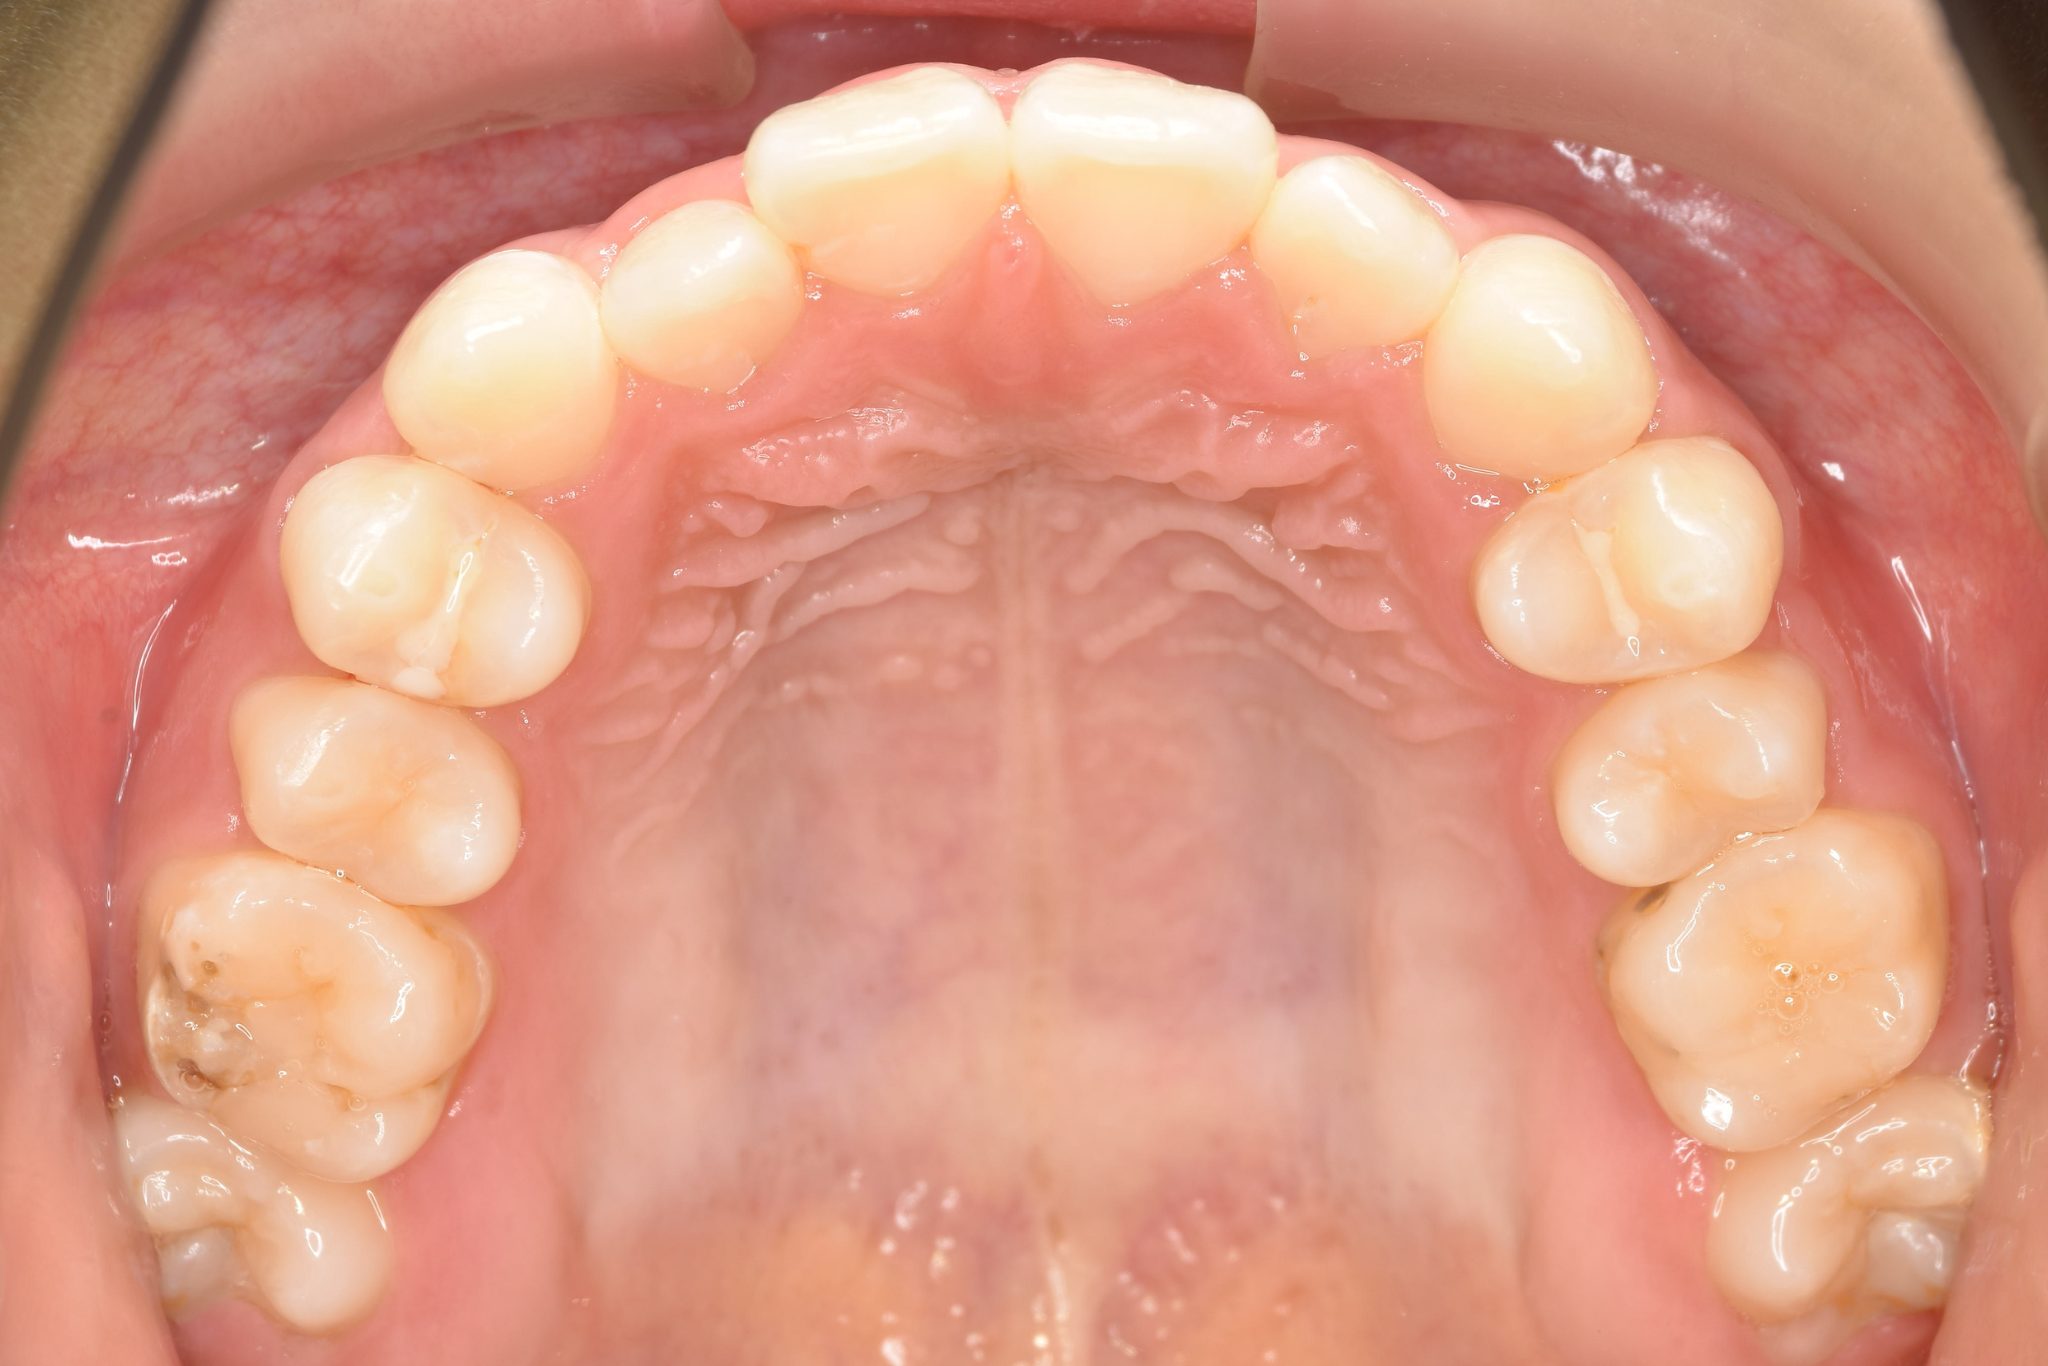

ビフォー

子どもの矯正治療|症例_169

主訴 歯並び|嚙み合わせ|口呼吸

施術内容 上顎急速拡大装置と下顎リンガルアーチを用いて上下顎骨を拡大した。

その後マウスピース型矯正装置で歯牙を配列し良好な咬合を獲得した。